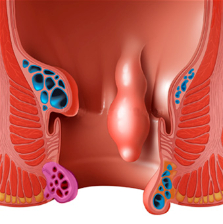

Piles

Hemorrhoids (HEM-uh-roids), also called piles, are swollen veins in the anus and lower rectum. Hemorrhoids are similar to varicose veins. Hemorrhoids can develop inside the rectum, called internal hemorrhoids. They also can develop under the skin ar